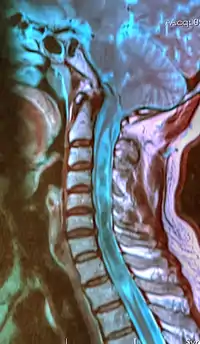

![]() | |

| A sagittal FLAIR MRI scan, from a patient with an Arnold–Chiari malformation, demonstrating tonsillar herniation of 7 mm. | |